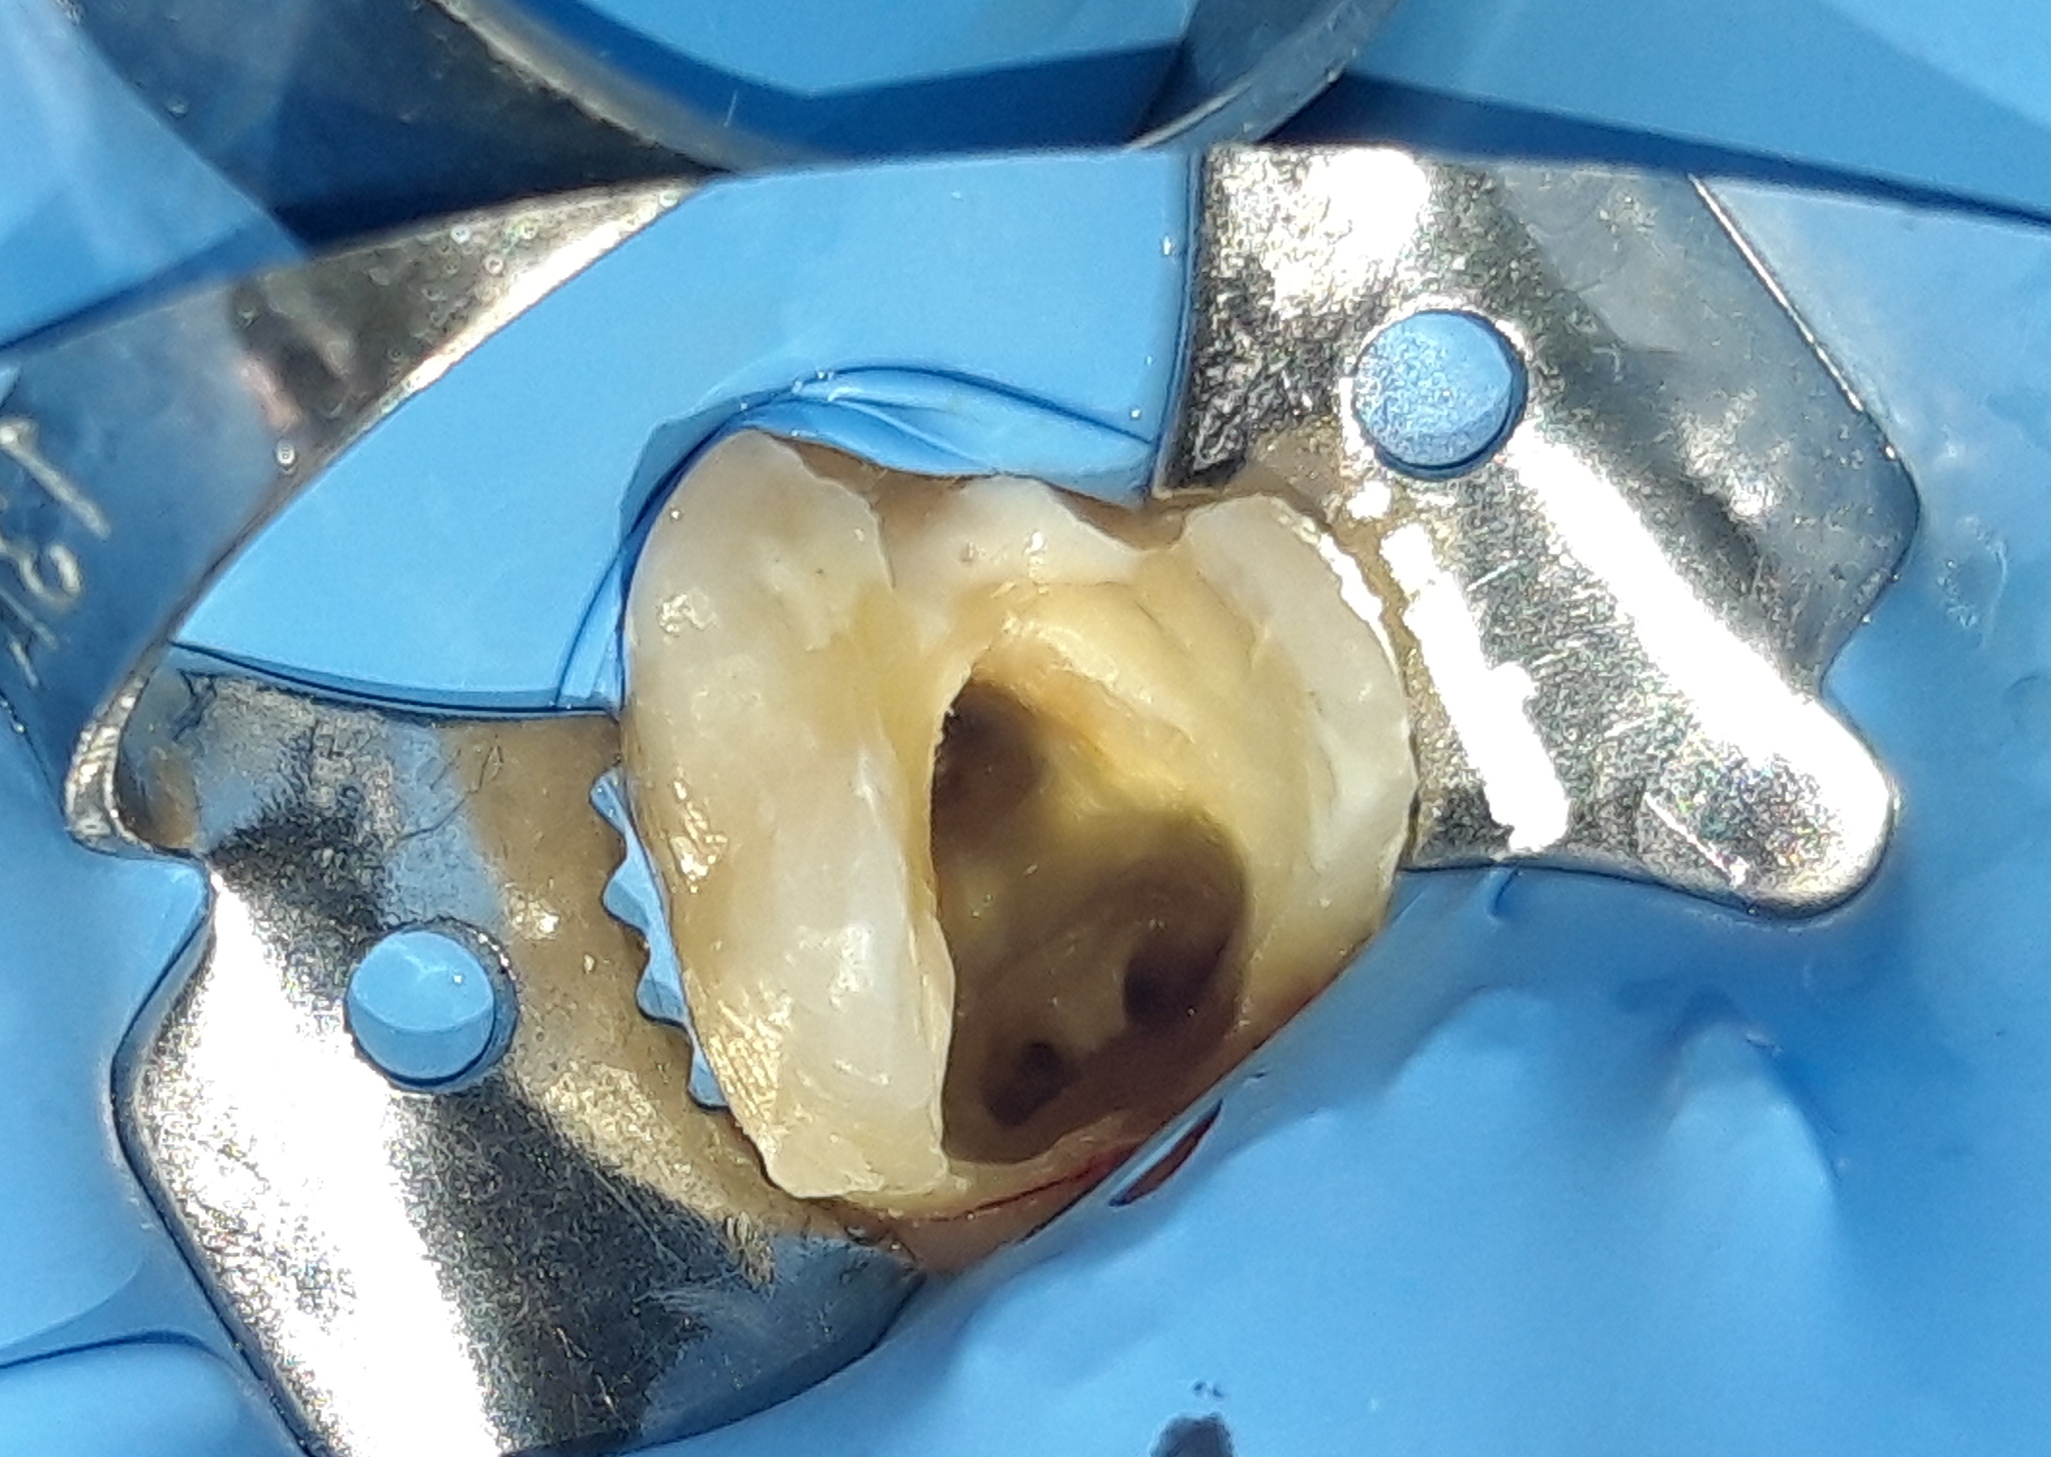

Αρχική κλινική εικόνα του μεγάλου οδοντικού ελλείμματος

Τελική κλινική εικόνα του ολοκεραμικού επένθετου στο γομφίο